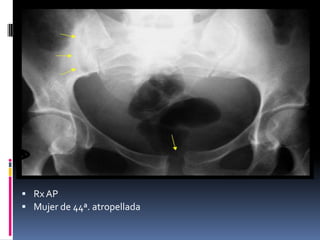

 Rx AP

 Mujer de 44ª. atropellada

 TC ventana de hueso

 Dx fractura del borde posterosuperior del ala sacra.

Subtipo B1.2